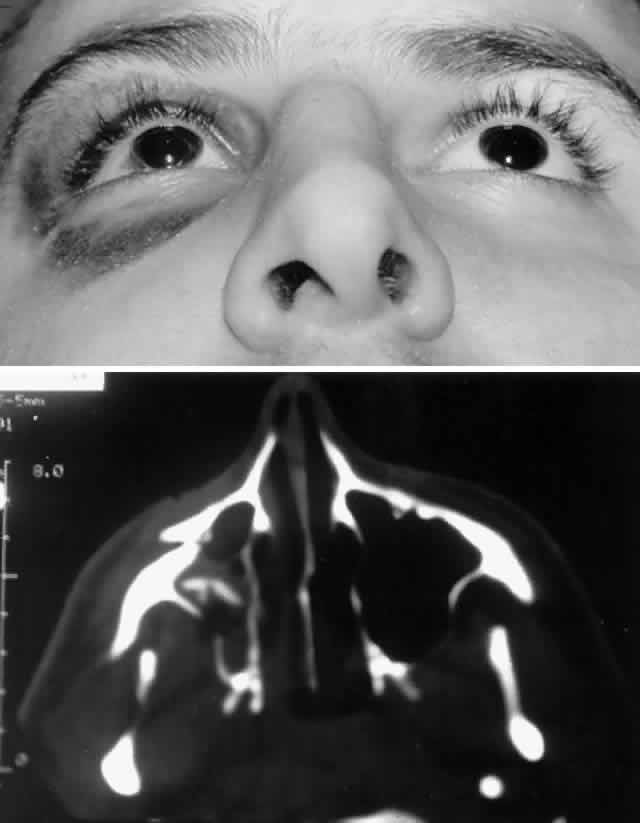

Methods of stabilization include interosseous wiring and miniplate fixation. Interosseous wiring is generally sufficient for repair of isolated orbital fractures resulting from low-energy injuries. Higher energy injuries, which result in multiple orbital rim fractures and comminution, benefit from rigid miniplate fixation to maintain a stable three-dimensional reconstruction and improve osteosynthesis (Figs. 8, 9, and 10). Miniplate fixation allows bridging of areas of extensive comminution. Miniplates come in various sizes (i.e., plate thickness [“profile”] and screw size) and shape. Miniplates generally have a profile of at least 1 mm and utilize screws equal to or greater than 1.5 mm, whereas microplates have profiles on the order of 0.5 mm and screw sizes of approximately 1 mm. Plates and screws of intermediate size are also available, and these appear to be ideal for orbital reconstruction. Most miniplates (and screws) are composed of corrosion-resistant metals, such as titanium or vitallium (an alloy of cobalt, chromium, and molybdenum). Because these metals are nonmagnetic, postoperative MRI is not contraindicated after reconstruction with these materials. These materials do produce some artifact on CT scan; however, this artifact is less than that noted with stainless steel, with titanium having the least artifact.

Fig. 8. A. Patient with right zygomatico-orbital fracture. Note flattening of right malar eminence and slight right lateral canthal dystopia. B. Axial CT scan shows displaced right zygomatico-orbital fracture.

Fig. 9. Repair of zygomatico-orbital fracture with rigid miniplate fixation, approached via a single transconjunctival incision with extended lateral canthotomy/cantholysis. A. Exposure and fixation of lateral (frontozygomatic) orbital rim fracture. B. Reduction and fixation of inferior orbital rim fracture. Orbital floor can also be explored via the same approach.

Fig. 10. A. Postoperative appearance of patient in Figure 8 showing excellent position of the globe and eyelid. B. Normal malar contour has been re-established.